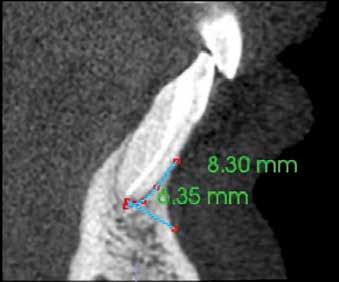

Egy fiatal hölgy, aki modellként dolgozik és emiatt nagy jelentőséget tulajdonít a saját fogai megőrzésének, a két középső alsó metszőfoga alatt kialakult duzzanat miatt kereste fel a rendelőnket. Vizsgálatot követően megállapítottuk, hogy a fogak mellett 20 mm szélességű tasak van jelen, amely az egyik alsó középső metszőfog disztális oldalától a másik alsó középső metszőfog disztális felszínéig terjed. Ebből az következik, hogy ezen a területen a teljes bukkális kortikális csontlemez leépült. Mindkét fog III. fokú mobilitással rendelkezett, amely tovább rontotta a kérdéses fogak várható prognózisát. Szenzibilitásvizsgálatot is végeztünk. A két alsó középső metszőfog esetében a páciens nem jelzett hidegingert, de a többi fog esetében fiziológiás választ adott. Periapikális röntgenfelvétel készült, amelyen nem mutatkozott meg a vélelmezett elváltozás (1. ábra). Ennek megfelelően CBCT-felvételt készítettünk, hogy jobban meg tudjuk vizsgálni a kérdéses területet. Ezen a felvételen már láthatóvá vált a vertikális és horizontális irányú csontpusztulás tényleges mértéke. A horizontális síkban készített metszeten a két alsó középső metszőfog körül megfigyelhető volt a bukkális kortikális csontlemez és a szivacsos csontállomány hiánya. A defektus szélessége 14,11 mm, a mélysége pedig 6,28 mm volt (2. a. ábra). A vertikális irányú metszeten láthatóvá vált, hogy a középső metszőfogak gyökerének bukkális oldalát nem fedi csont, és ez a defektus már a gyökércsúcsok alatti területre is kiterjedt (2. b–c. ábra)

1. ábra: Kiindulási röntgenfelvétel. – 2. a–c. ábra: A horizontális irányú metszeten kiterjedt csontpusztulás jelei láthatóak (a), a vertikális irányú metszeteken mindkét középső metszőfognak megfelelően észlelhető a csontpusztulás (b–c).